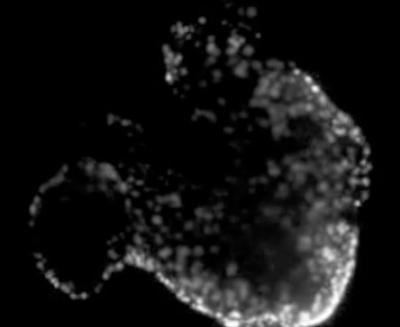

After testing that their treated hearts were sufficiently softened or stiffened, they fluorescently labeled a small percentage of cells in the heart so they could quantify how hard the hearts were beating while looking at them under a microscope.

"When we treat the hearts with a chemical that breaks down the collagen," Majkut said, "we can directly see that the hearts aren't contracting as much because the labeled cells aren't getting as close to each other as they did before."